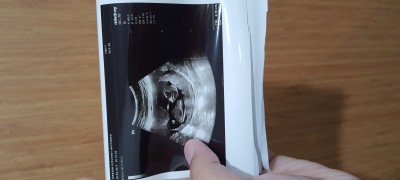

Bugün ikili test için geldik  13 haftalık olmuşuzz.  Cinsiyet tahmininde bulunacak arkadaş var mi :) diğer ay geldiğimizde bakacakmisiz. Doktorumuz öyle dedi. Haftasına göre herseyi iyiymiş çok şükür

Gebelik haftası 13+0

Paşa paşa uzanmış maşallah sübhanallah erkek diyesim geldi  inşallah sağlıcakla gelir minik

Kız bebek bu bence

Ben kıza benzettim kız bebek sanırım